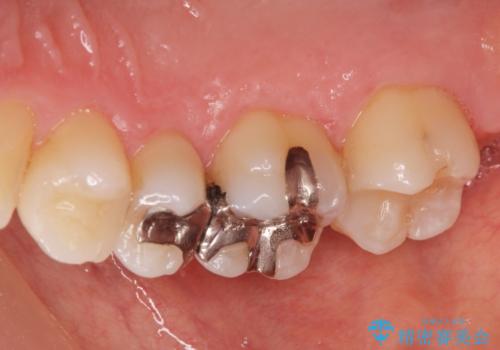

- 銀の詰め物を白くしたいとの事で来院。

拡大鏡下で詰め物を外しう蝕がないことを確認して、e-maxインレーにて治療しました。

- e-maxインレー 7.7万円 費用は治療当時の料金となります